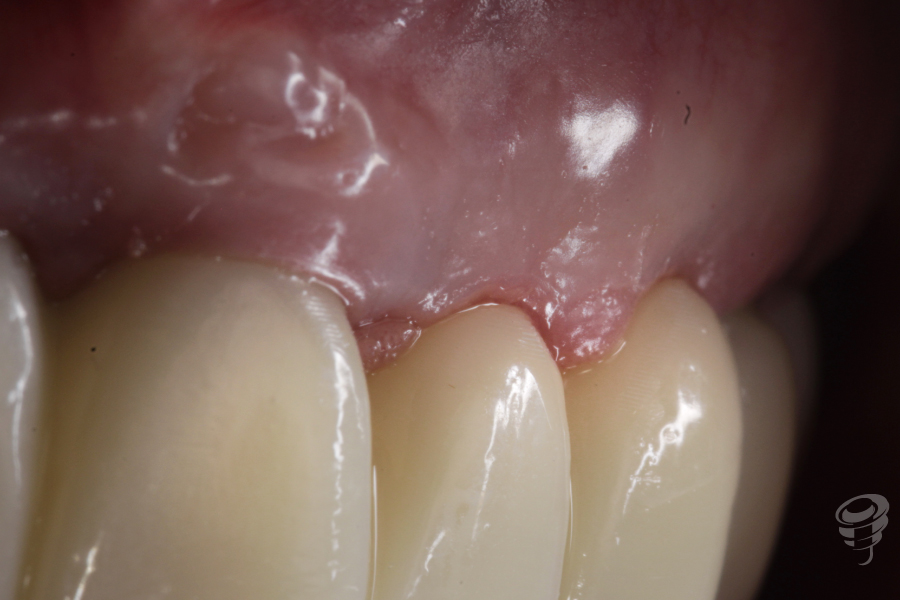

Situación prospto perio después de 2 meses con los perfiles de emergencia personalizados

Figura 14

Figura 15

Desgastamos la zona estética de la prótesis (11-21) para crear espacio y así conseguir la recolocación del margen gingival.